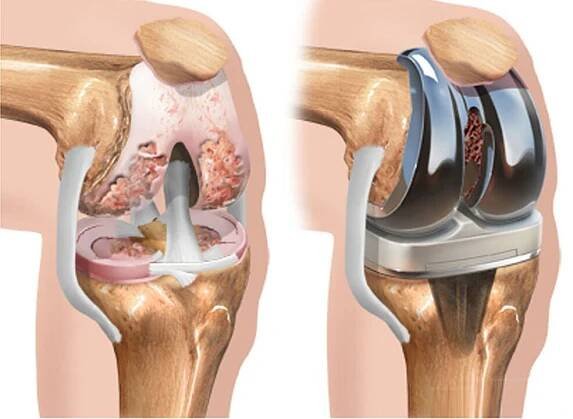

Gonartróza, osteoartróza kolenního kloubu neboli artróza kolenního kloubu je degenerativní onemocnění kolenního kloubu. Gonartróza způsobuje bolest a ztuhlost v oblasti kolene, a může komplikovat každodenní činnosti, jako je vstávání ze židle nebo i krátké procházky.

Gonartróza neboli degenerace kolenního kloubu je jedním z nejčastějších onemocnění kloubů u dospělých. Podívejte se, jak ji léčit.

Artróza kolenního kloubu (Gonarthrosis)